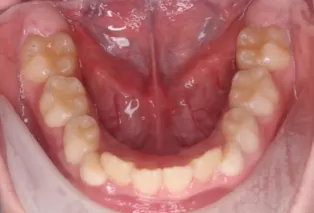

Patient: Female, 11 years old

Conditions: Deep overjet, upper anterior teeth protrusion

Treatment Device: K3

Intraoral photos